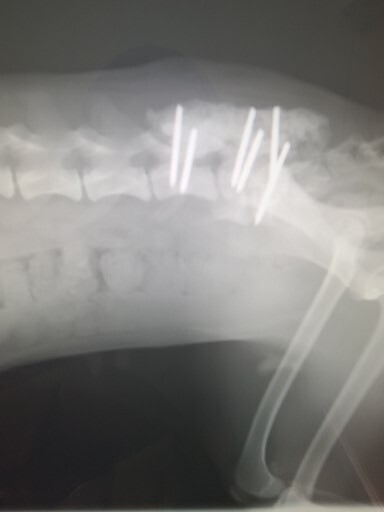

骨の状態は良好!(2月14日)

動物病院より掲載許可取得済

術後の骨の状態は良好で、体重も順調に増えているとのこと。本当に良かったです。しかも、外でお散歩まで後28日と報告しましたが、なんと少しだけなら、明日から毎日外へのお散歩OK! 1か月早く許可が出ました。